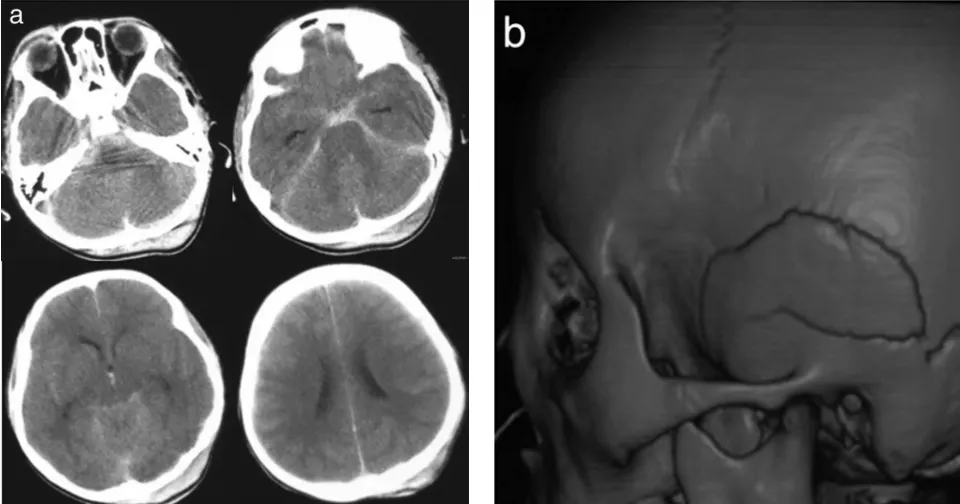

一场突发交通事故导致8岁男性患儿小明陷入中度昏迷状态。后续...

当地医院的CT检查结果带来沉重一击:提示右侧小脑半球出血。仅...